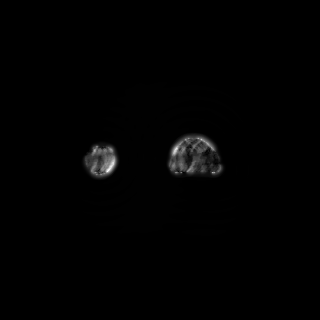

where denotes element-wise (Hadamard) product, and and denote the forward and the inverse Fourier transforms, respectively. The binary matrix denotes the sampling operator that embodies the Cartesian trajectories through which the measurements were obtained; we refer to the rate of decimation induced in -space as the acceleration factor ().

We consider the following two inverse problems: (i) Superresolution (SR), consisting of reconstructing a sharp image from measurements containing only the central low frequencies obtained by using the mask as in Fig. 2 (a & c); and (ii) Dealiasing, in which the obtained mask results in an aliasing artifact due to a coarser sampling in the phase-encoding direction. We use the masks displayed in Fig. 2(b & d). The inverse problem consists of restoring a finer sampling grid in the phase-encoding direction. Throughout the paper, we denote the experiments specifying the task name (one of the two tasks above) and the acceleration factor.